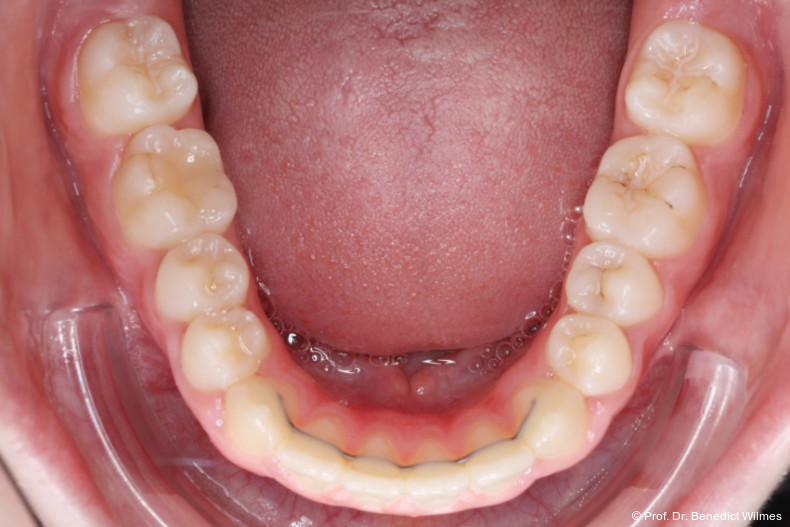

Nach erfolgreicher Expansion und Molaren­intrusion wurde eine Multibracket-Therapie zur Ausformung und Koordination der Zahnbögen durchgeführt (Abb. 8a–f). Nach Abschluss der aktiven Behandlungsphase wurden die Apparaturen entfernt und festsitzende Retainer im Ober- und Unterkiefer eingesetzt (Abb. 9a–k).